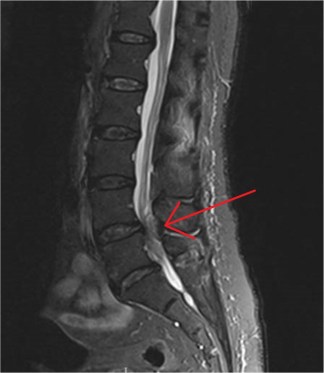

Now let’s talk about the prognosis. Thankfully if caught early surgical intervention is typically indicated and can lead to a full recovery (yay). Unfortunately about 20% of people still have a bad outcome despite surgery, so it isn’t a completely fixable thing. The good news here is that unlike the spinal cord, the cauda equina can heal, it nerve growth is possible so the most important aspect for a good outcome is the severity and duration of compression upon the damaged nerve(s). Generally, the longer the time before intervention to remove the compression causing nerve damage, the greater the damage caused to the nerve(s). Below we show another MRI, this time highlighting the damage caused by an abscess, which we’ve highlighted with a red arrow.

An epidural abscess causing cauda equina syndrome (Red arrow).